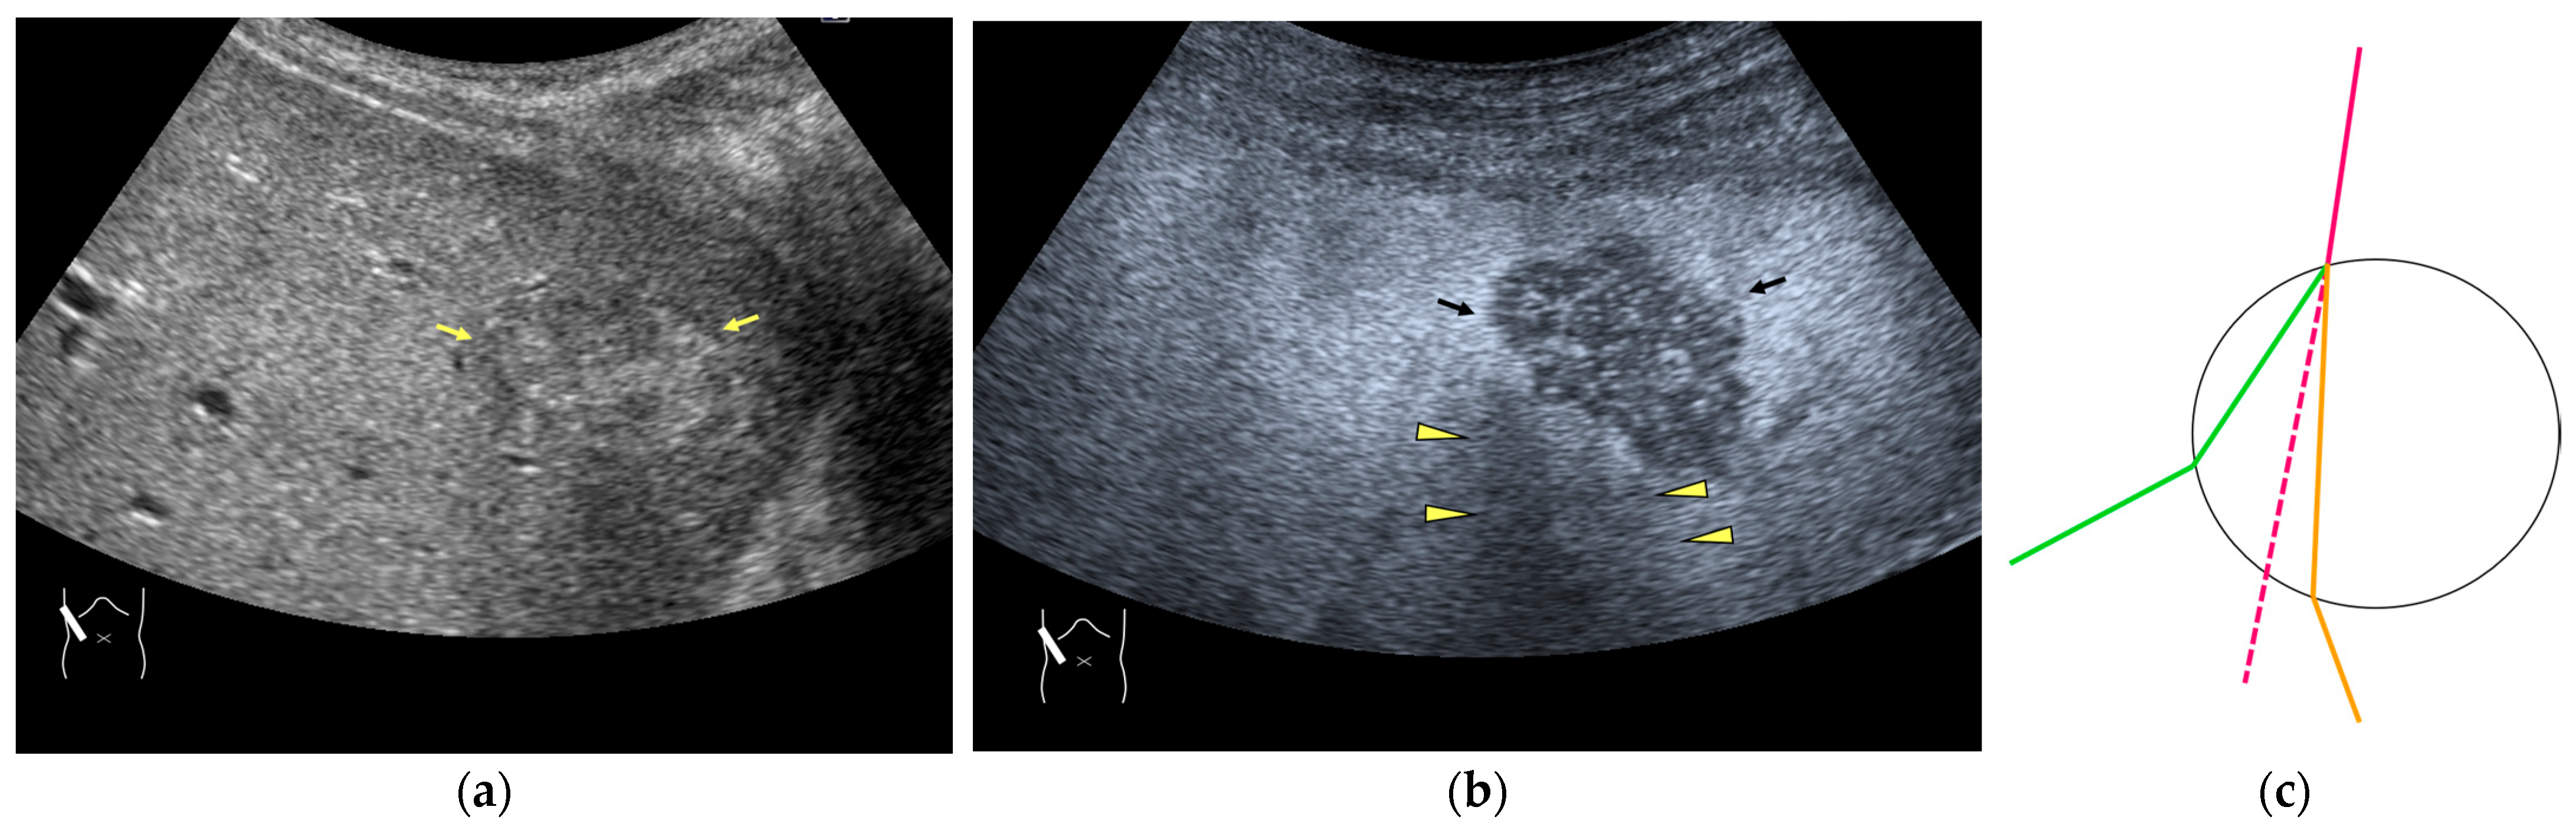

Figure 12.

Manhole-like defect in hemangioma: (a) gray-scale US of the case (arrows: hemangioma); (b) CEUS shows a cotton wool appearance in the periphery of the lesion (arrows): (c) the lesion shows a complete defect in the lesion during observation (arrows); (d) a reasonable explanation of this phenomenon. In hemangioma, destroyed microbubbles are not quickly replaced because of the low blood flow velocity, mimicking a wash-out phenomenon.